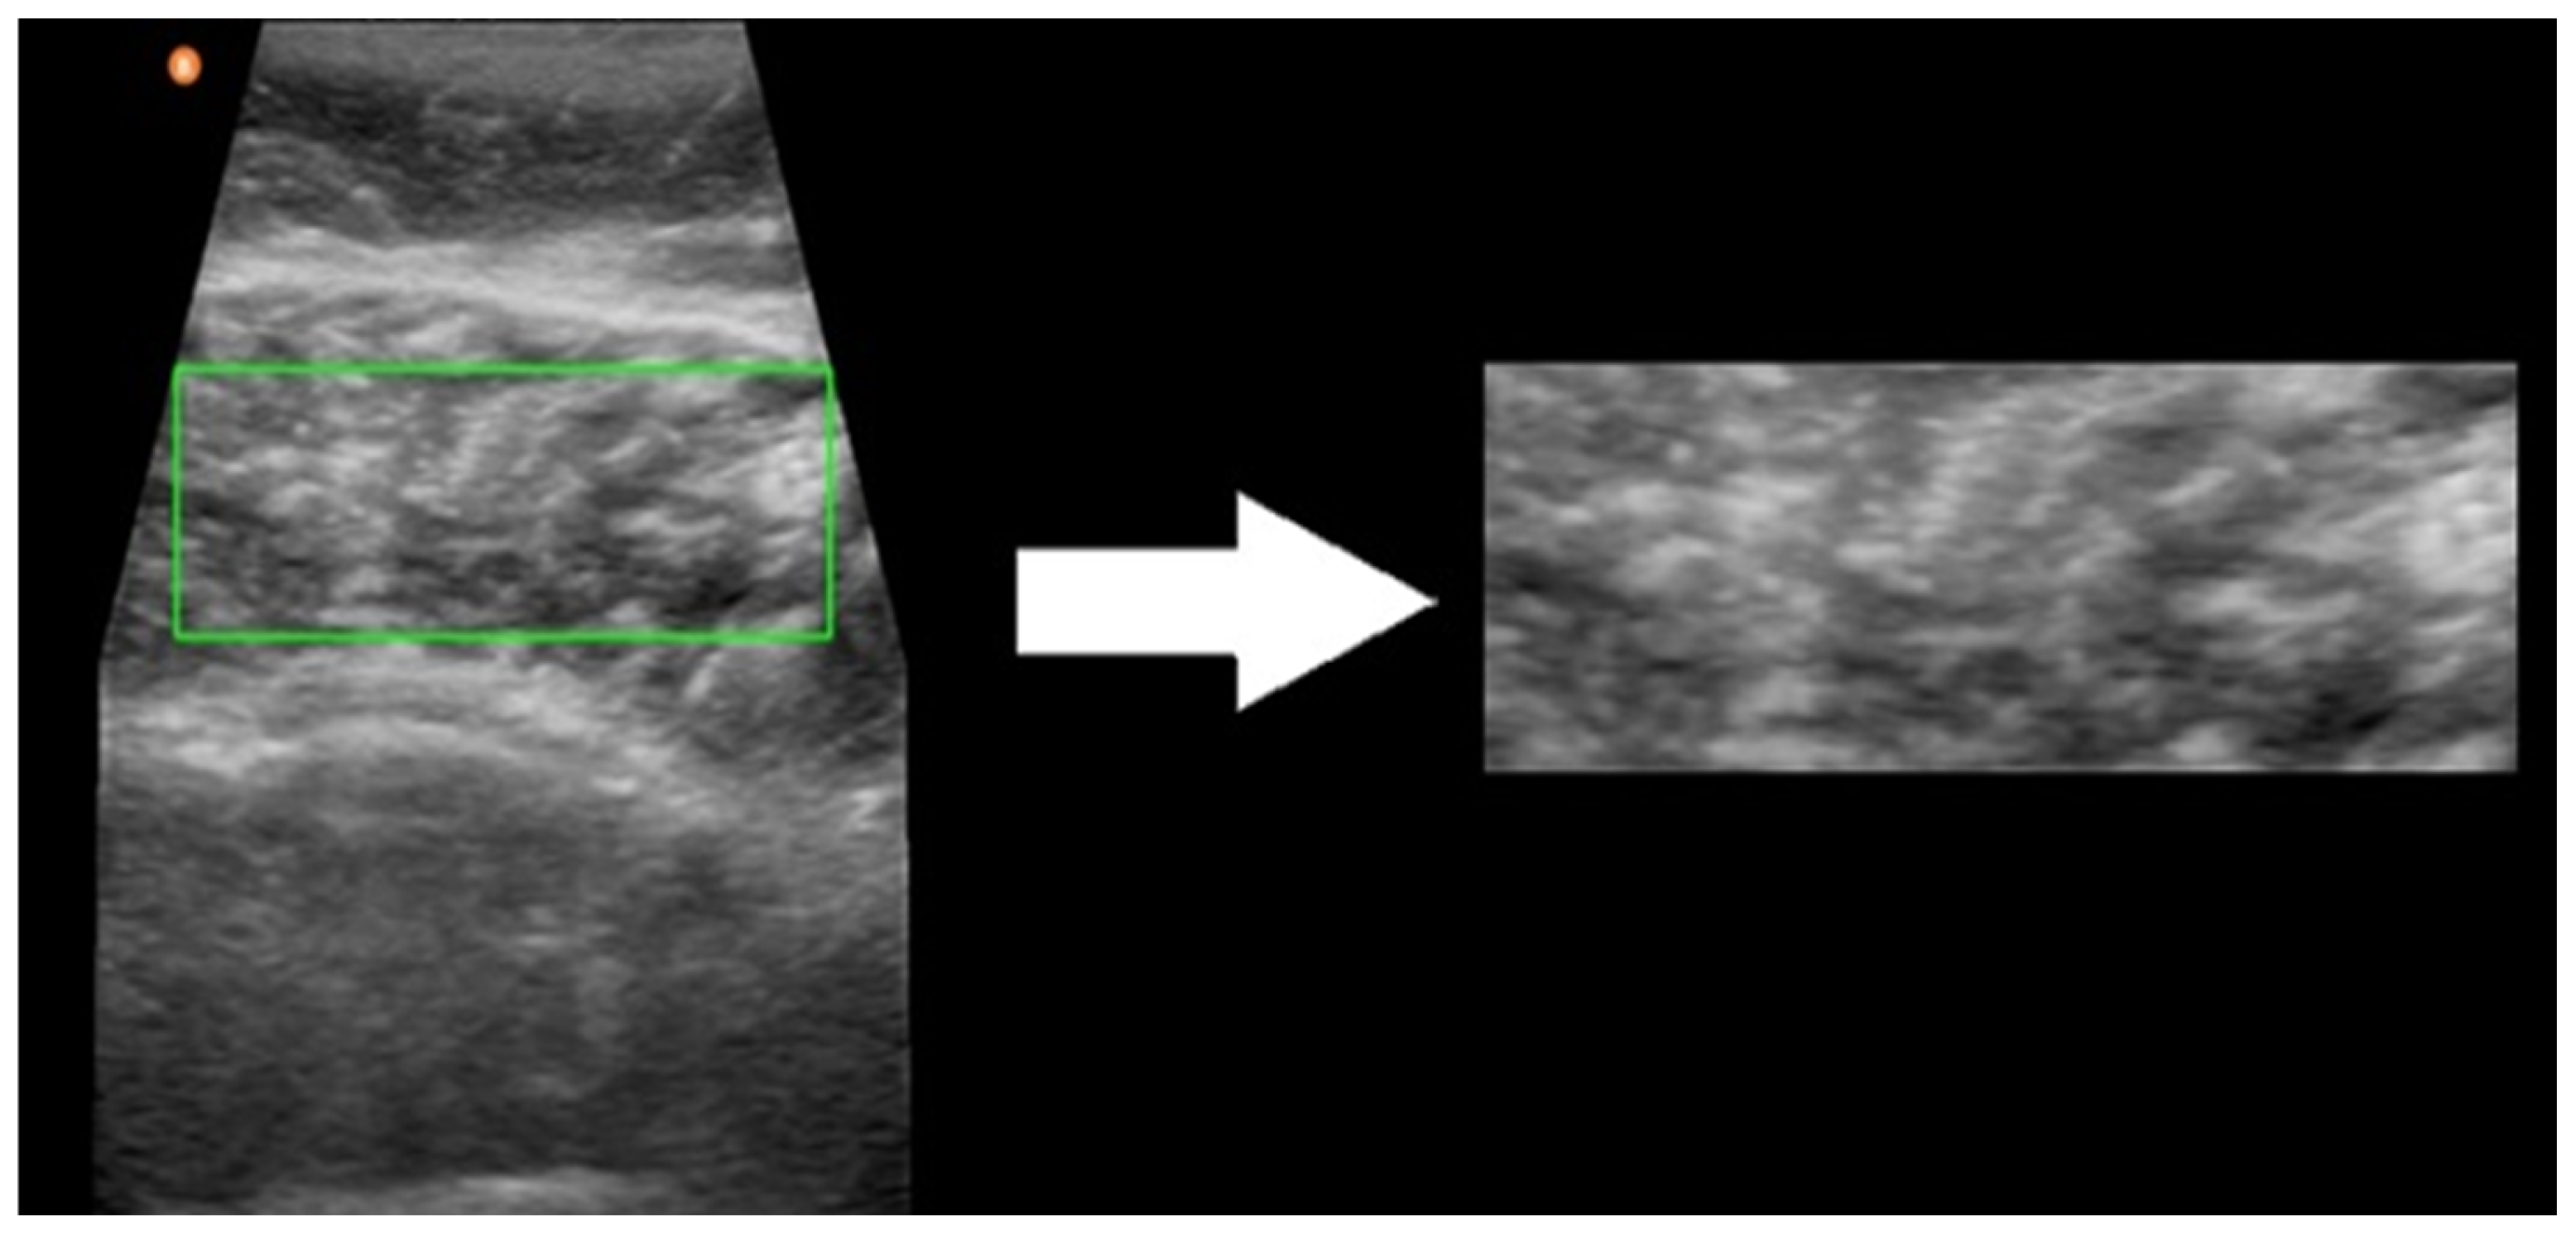

2.3. Data Collection